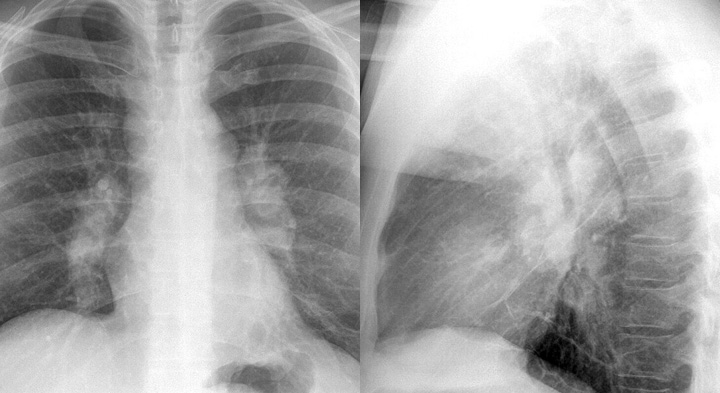

Gallery Sarcoid Sarcoid Case 3 PA & Lat

Case 3 PA & Lat